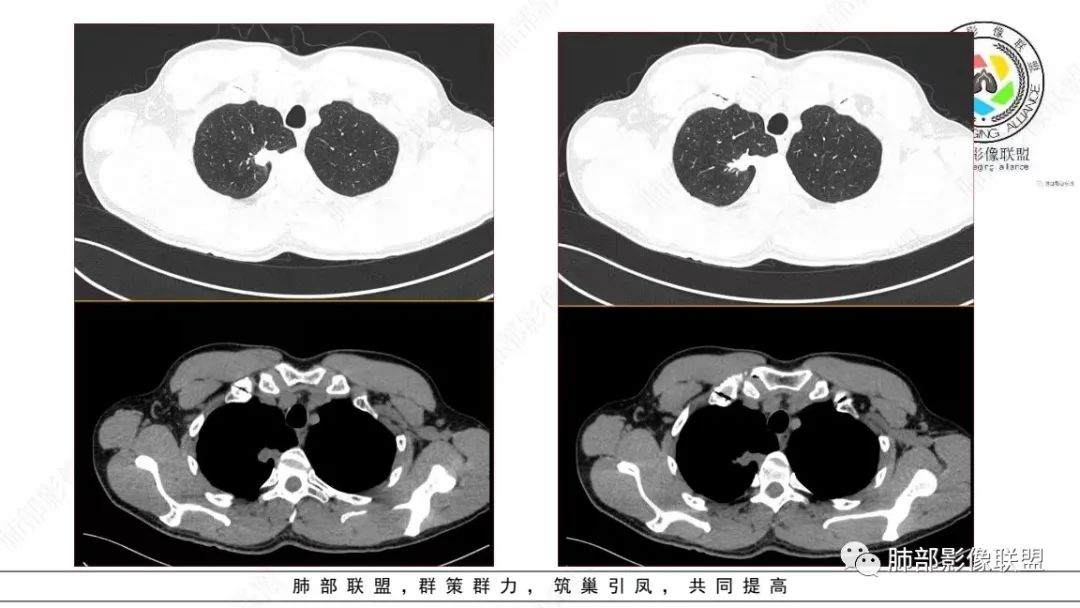

细支气管腺瘤的病理要点中,很重要的一点就是双层细胞。返回来看影像,这个病变还是很有特点的,诊断结核确实有点不合适。一点点的看。

仔细看,里面是有低密度的。平扫CT值也很低,才16HU。

增强也很有特点。这些低密度,是有延迟强化特点的。

平扫低密度,就这个病变而言,我们最容易想到的:干酪性坏死、黏液。而延迟强化。所以这个病变是不符合干酪性坏死的表现的。很多平直凹陷的地方,与胸膜宽基底接触,是否存在胸膜牵拉不详,需重建看看。说明这个病变是有收缩力的。里面含有一部分纤维。当然,含有纤维的,肿瘤的肌成纤维可以,上皮间质转换可以,慢性炎也可以,好多病变里面可以有纤维。干酪样坏死,是不会强化的。延迟强化,肉芽肿可以,纤维比较多的或者黏液多的也可以。

还是和病变成分有关。在肿瘤当中,或者上皮间质转换比较明显等,可以有不同的强化方式。当然也可以表现为延迟强化,可以动脉期明显强化。和肿瘤的具体类型,以及具体病变的病理成分有关。多层面观察,病变是明确有细支气管进入的,而且明确的有铸型的低密度粘液栓。